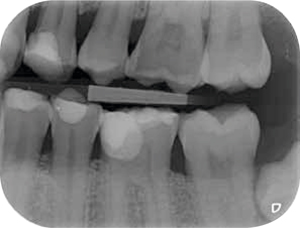

Röntgenonderzoek

Röntgenologisch onderzoek laat meerdere problemen zien. Onder andere een forse zwarting apicaal van element 12 met het beeld passend bij periapicale problematiek en een verleden van apicale chirurgie (afbeelding 8-12 ).

Afb. 11-12

Bitewings. Met de initiële fase is al een aanvang gemaakt.